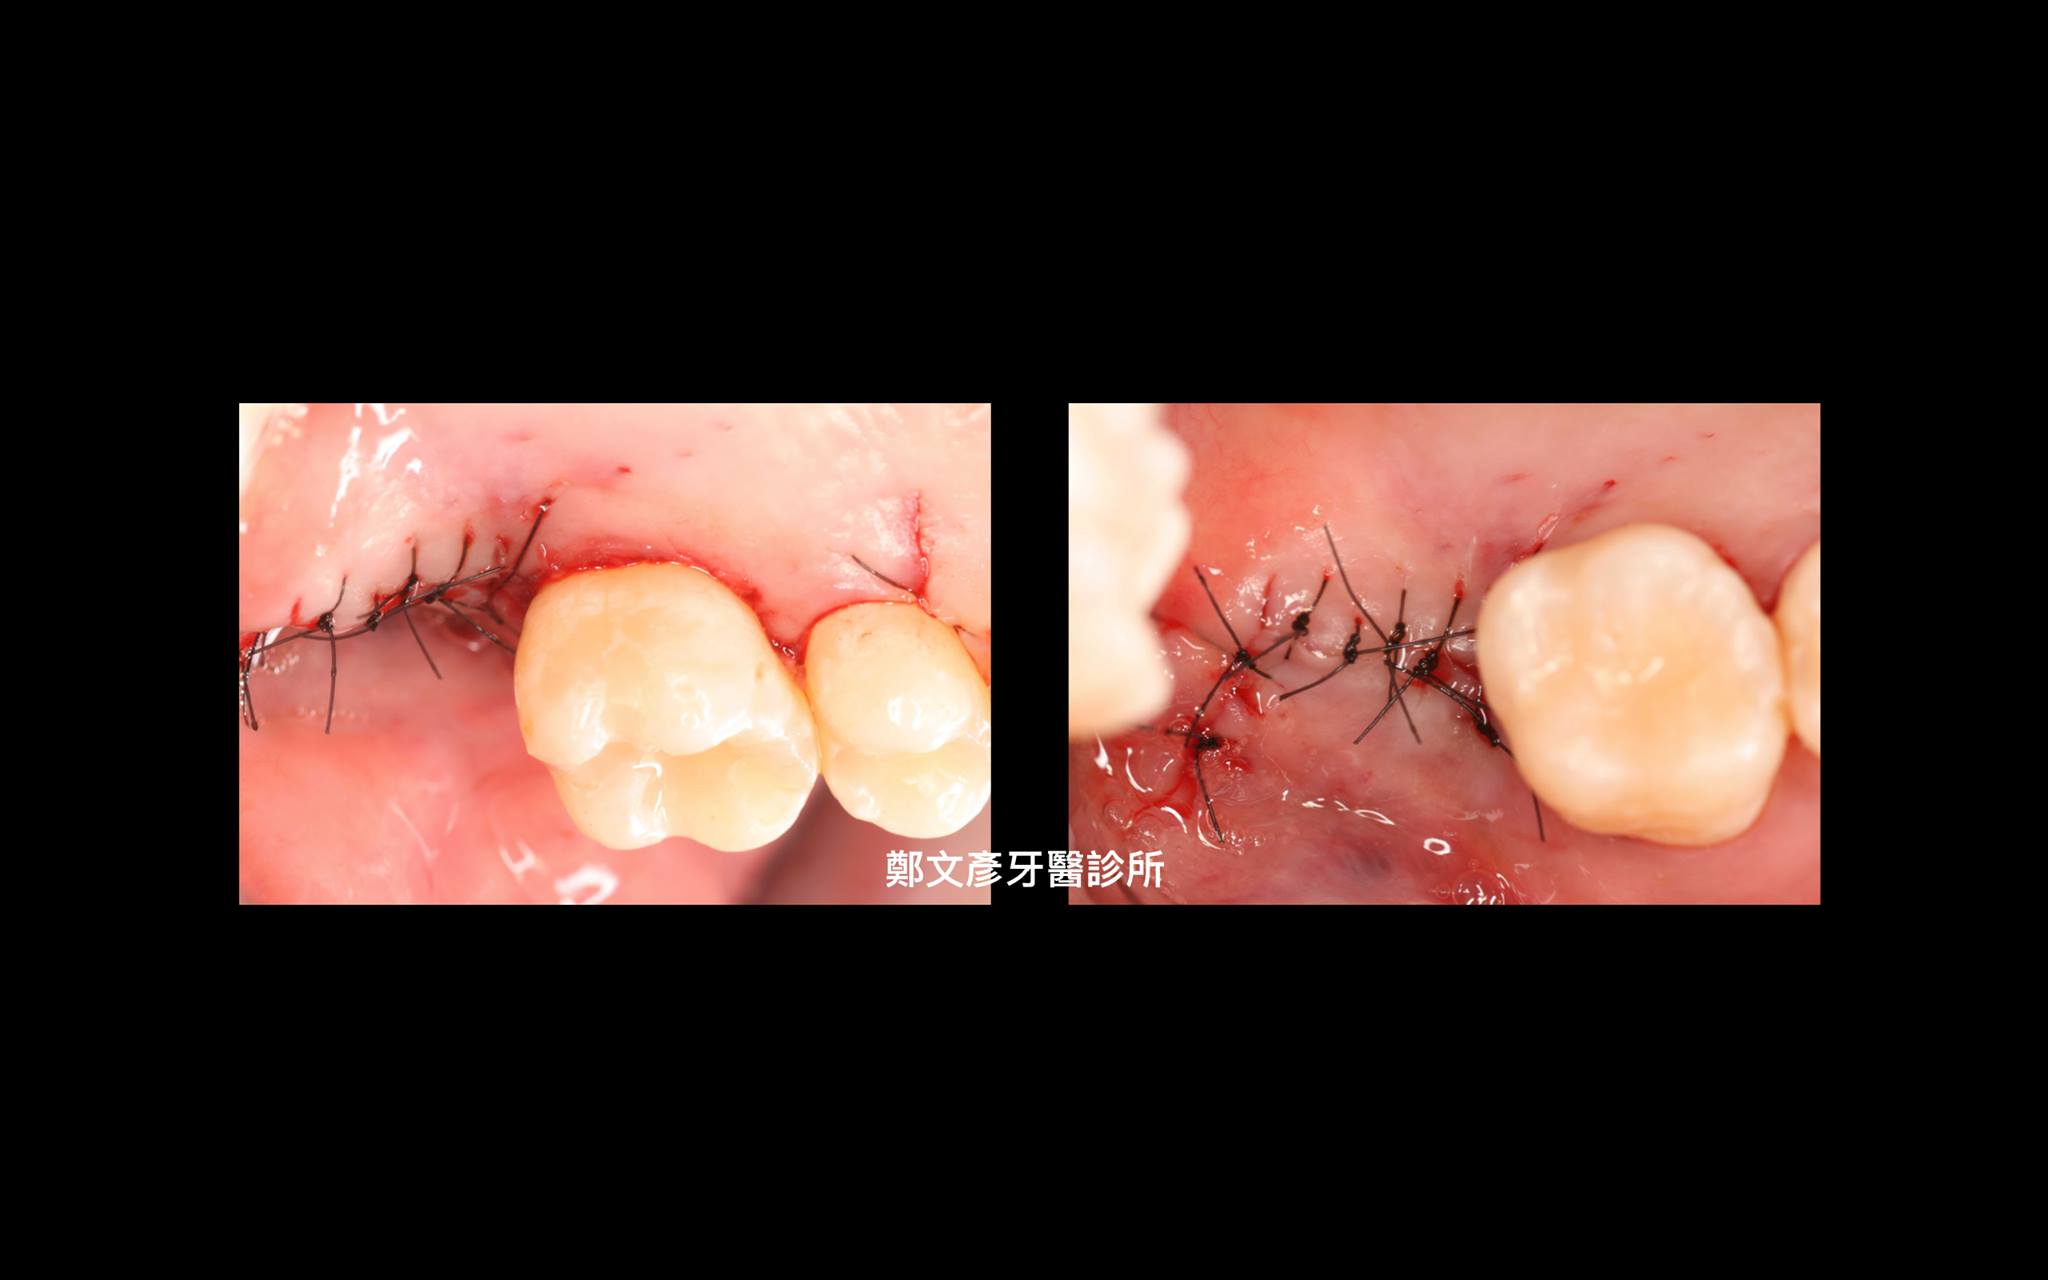

牙周再生補骨手術 ( GTR )

再生補骨